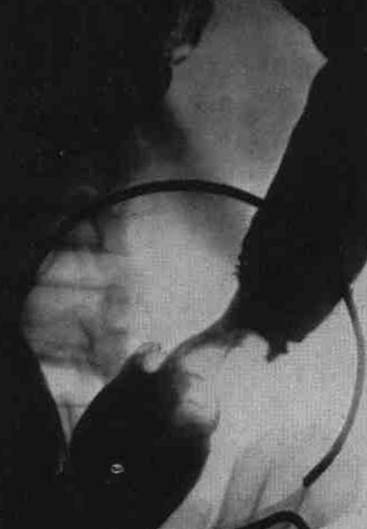

Вопросы к рис. 1:

1) Что такое ирригоскопия?

2) Назовите основной рентгенологический признак рака сигмовидной кишки на прицельной рентгенограмме при ирригоскопии. Покажите его.

Рис. 1

1) Ирригоскопия – метод рентгенологического исследования толстой кишки путем ретроградного (с помощью клизмы) заполнения ее рентгенконтрастным веществом (взвесью сульфата бария).

2) На прицельной рентгенограмме сигмовидной кишки определяется циркулярное сужение ее, контуры суженного участка неровные, определяется «дефект наполнения».